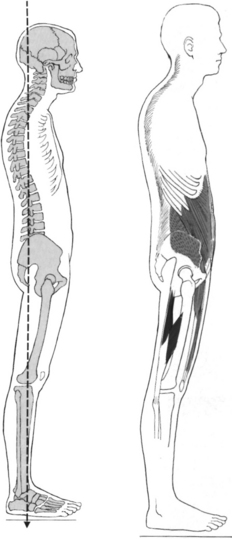

This text discusses musculoskeletal pain syndromes arising from tissue alterations that are caused by movement. Movement is considered a system that is made up of several elements, each of which has a relatively unique basic function necessary for the production and regulation of movement. Various anatomic and physiologic systems are components of these basic elements (Figure 2-1). To understand how movement induces pain syndromes, the optimal actions and interactions of the multiple anatomic and physiologic systems involved in motion must be considered. The optimal function and interaction of the elements and their components are depicted in the following kinesiologic model.

The elements of the model are (1) base, (2) modulator, (3) biomechanical, and (4) support. The components that form the base element, the foundation on which movement is based, are the muscular and skeletal systems. The components of the modulator element regulate movement by controlling the patterns and characteristics of muscle activation. The modulator element of motion is the nervous system, because of its regulatory functions (described in the sciences of neurophysiology, neuropsychology, and physiologic psychology). Components of the biomechanical element are statics and dynamics. Components of the support element include the cardiac, pulmonary, and metabolic systems. These systems play an indirect role because they do not produce motion of the segments but provide the substrates and metabolic support required to maintain the viability of the other systems.

Pathokinesiology is described by Hislop as the distinguishing clinical science of physical therapy, and it is defined as the study of anatomy and physiology as they relate to abnormal movement.25 Based in part on word construction and in part on clarification of causative factors, pathokinesiology emphasizes abnormalities of movement as a result of pathologic conditions. The pathokinesiologic model (Figure 2-2) depicts the role of disease or injury as producing changes in the components of movement, which result in abnormalities of movement. In the Nagi model of disablement,45 disease leads to impairments that cause functional limitations with the possible end result of disability. Impairments are defined as any abnormality of the anatomic, physiologic, or psychologic system. Therefore abnormalities of any component system or of any movement are considered impairments.

A common belief is that movement impairments are the result of pathologic abnormalities, but the thesis of this text is that movements performed in daily activities can also cause impairments that eventually lead to pathologic abnormalities. Therefore a different model is proposed to characterize the role of movement in producing impairments and abnormalities. The empirical basis of this model stems from observations that repetitive movements and sustained postures affect musculoskeletal and neural tissue. The cumulative effect of repetitive movements is tissue damage, particularly when the movements deviate from the optimal kinesiologic standard for movement. Human movements involve similar internal and external forces as do mechanical systems.49 In mechanical systems, maintaining precise movement is of such importance that the science of tribology is devoted to the study of factors involved in movement interactions. Tribology is defined as the study of the mechanisms of friction, lubrication, and wear of interacting surfaces that are in relative motion.1 Based on the similarities of biomechanical and mechanical systems, the premise for ensuring the efficiency and longevity of the components of the human movement system is maintaining precise movement of rotating segments. Although the adaptive and reparative properties of biological tissues permit greater leeway in maintaining their integrity than do nonbiologic materials, it is reasonable to assume that maintaining precise movement patterns to minimize abnormal stresses is highly desirable.

Therapists and other clinicians involved in exercise prescription believe that repeated movements can be used therapeutically to produce desired increases in joint flexibility, muscle length, and muscle strength, as well as to train specific patterns of movement. All individuals who participate in exercise accept the fact that repeated movements affect muscle and movement performance. Thus these individuals should also accept the idea that repeated motions of daily activities, as well as those activities of fitness and sports, may also induce undesirable changes in the movement components. Stretching and strengthening exercises performed for shorter than 1 hour are believed to produce changes in muscular and connective tissues. However, repeated movements and sustained postures associated with everyday activities that are performed for many hours each day may eventually induce changes in the components of the movement system. The inevitable result is the development of movement impairments, tissue stress, microtrauma, and eventually macrotrauma. In accordance with this proposed theory, the effects of repeated movements and sustained postures modify the kinesiologic model so that it becomes a kinesiopathologic model (Figure 2-7), that is, a study of disorders of the movement system.